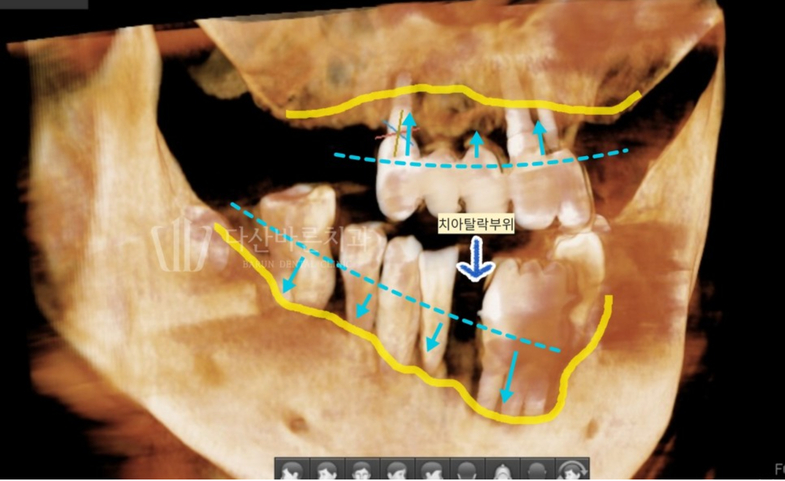

(Ảnh bên dưới) Chúng ta hãy xem kỹ hơn bức ảnh toàn cảnh 3D.

Bạn có thể thấy đường viền nướu vốn đáng ra phải là

đường chấm màu xanh lam nay đã chìm xuống đường

viền màu vàng đậm nằm ở đầu chân răng.

Khi nướu đã tụt đến mức này thì việc răng rụng cũng không có gì lạ,

răng tự nhiên bên cạnh đã ăn sâu vào chân răng nên sẽ rụng sớm thôi.

(Hình bên dưới) Nếu quan sát tình trạng viêm xung quanh trụ implant,

bạn có thể thấy xương nướu ở vùng răng cấy ghép phía dưới đặc biệt bị lõm xuống so với các vùng khác.

(Vạch liền màu vàng là đường xương nướu)

Ngoài ra, xác nhận xương nướu răng hàm trên đã tụt xuống đáng kể, chỉ bằng một nửa so với trụ implant.

Cả hàm trên và dưới đều là những biểu hiện điển hình của viêm quanh implant.

Tôi sẽ gợi ý cho bạn ở hình bên dưới.

(Đường liền màu vàng là đường xương nướu nâng đỡ răng và chân răng implant)

Như đã giải thích ở trên, cấy ghép ① và ②

có xương nướu đã tan chảy hơn 1/3 chiều dài của trụ implant cần phải được loại bỏ.

Ở phần ① và ②, như trong ảnh,

độ sâu của xương ổ răng bị mất sâu và lan rộng,

do đó thay vì trồng lại implant ở khu vực đó,

implant được trồng ở xương ổ răng xung quanh tương đối khỏe mạnh

và cầu răng implant được kết nối . Bạn có thể lên

kế hoạch cho phương pháp điều trị ‘cầu răng implant’.

Trong trường hợp cấy ghép số ③,

có thể xây dựng kế hoạch điều trị để ngăn ngừa tình trạng

viêm nặng hơn và mất xương nướu thêm thông qua phẫu thuật thẩm mỹ

Implant mà không cần tháo implant đã cấy và để cứu implant hiện tại càng nhiều càng tốt.